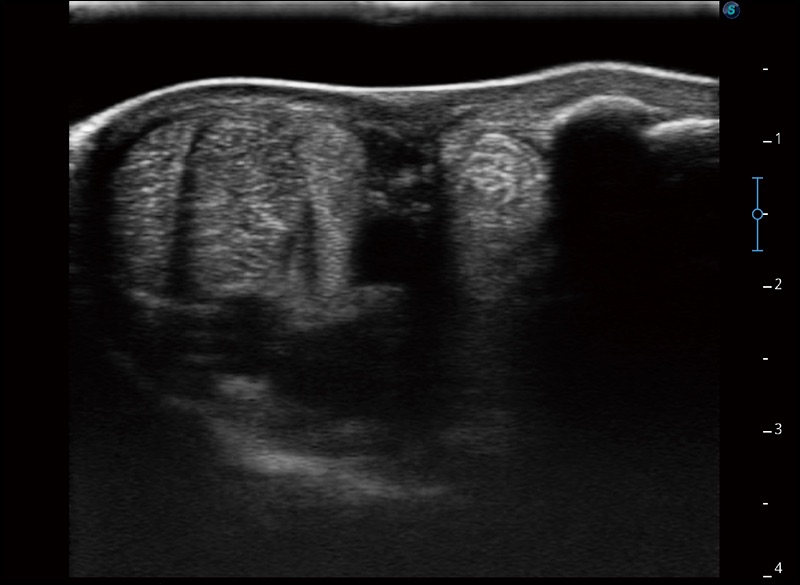

α1卓越的图像质量和便捷的工作流程,使每位宠物医生都能轻松扫查。其全面的兽用应用功能和紧凑型的结构设计,可以满足动物检查的多种需要。专业的预设检查模式和多领域测量软件包有助于为不同类型的动物提供检查, 让宠物医生能够出色的完成工作。

空间复合成像

优化不同角度的图像